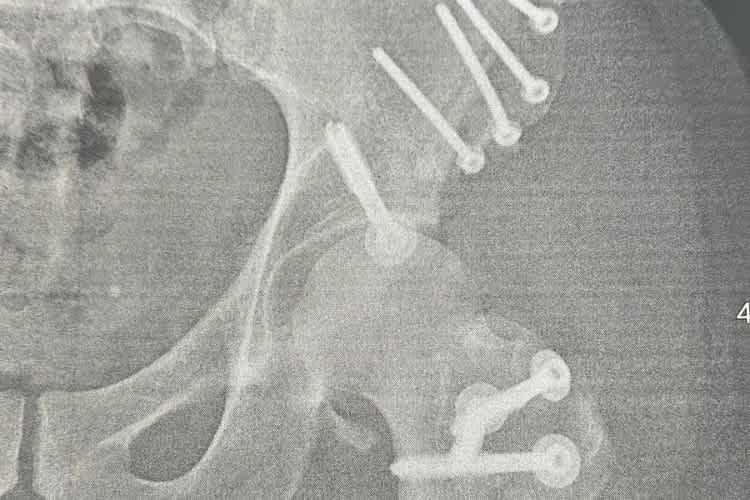

Gute Nachrichten gab es für ihn bei einem kürzlichen Kontrolltermin, bei dem die Hüfte gecheckt wurde. "Der Heilungsverlauf sieht gut aus. Die Schrauben sitzen gut und es befindet sich alles noch dort, wo es hingehört", berichtete Dilger. "Aktuell darf ich die Hüfte und das Bein mit 20 kg belasten und ab jetzt die Belastung um wöchentlich 10 kg steigern." Der gute und planmäßige Heilungsverlauf eröffnet neue Möglichkeiten in der Reha und für die Rückkehr aufs Motorrad. "Der weitere Saisonverlauf ist offen", so der 33-Jährige. "Ich kann endlich voll mit der Physiotherapie beginnen, da das Bein jetzt vollumfänglich bewegt werden kann. In etwa vier Wochen werde ich das Bein voll belasten können, dann sieht man weiter."